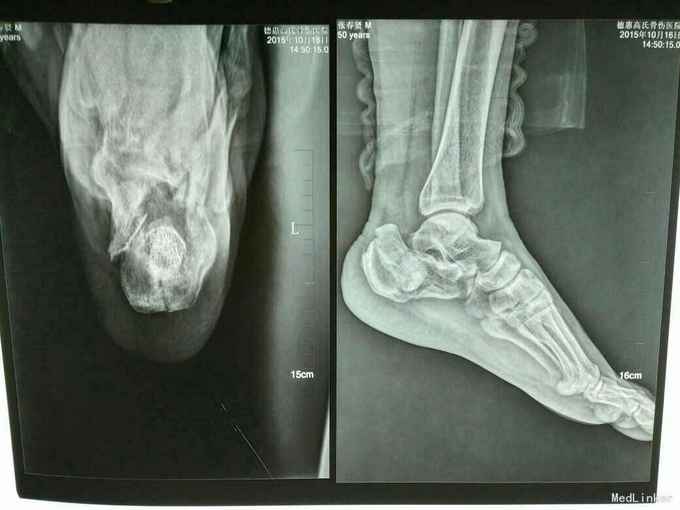

双足跟骨骨折

摔伤致双足跟部疼痛.肿胀.活动受限1小时

双足跟处肿胀,畸形明显,可触及骨擦感及异常活动,

双足跟骨骨折,手术治疗,